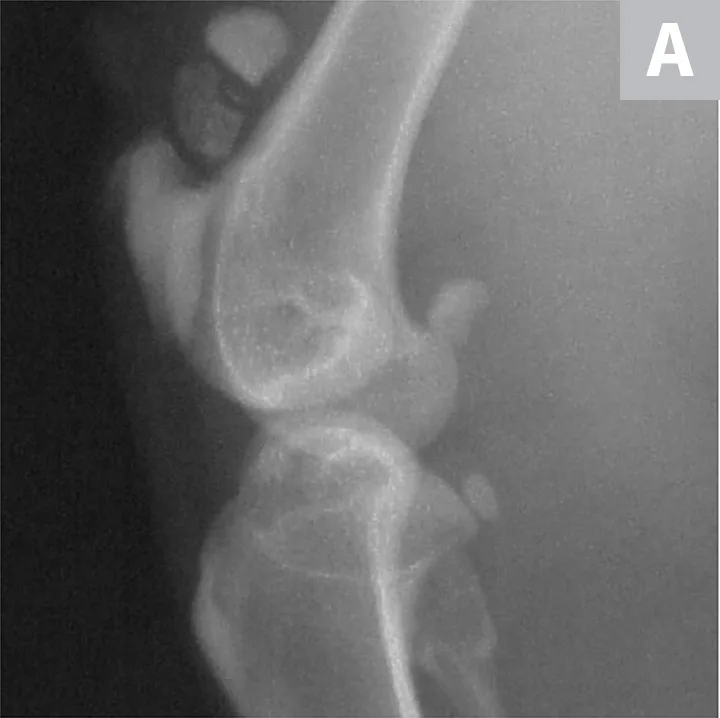

Serial radiographs of the pelvic limbs were taken periodically to monitor progression of the patellar fractures. Comparative orthopedic radiographs (Figure 3) 2 and 8 years after initial presentation revealed persistence of patellar fractures, with fragmentation, progressive sclerosis, and osteophytosis of the left patella.

Radiographs of the patellar fractures taken 2 years (A, left stifle; B, right stifle) and 8 years (C, left stifle; D, right stifle) after initial presentation. Progressive fragmentation and osteophytosis of the left patella and displacement of the right patellar fragments can be seen.